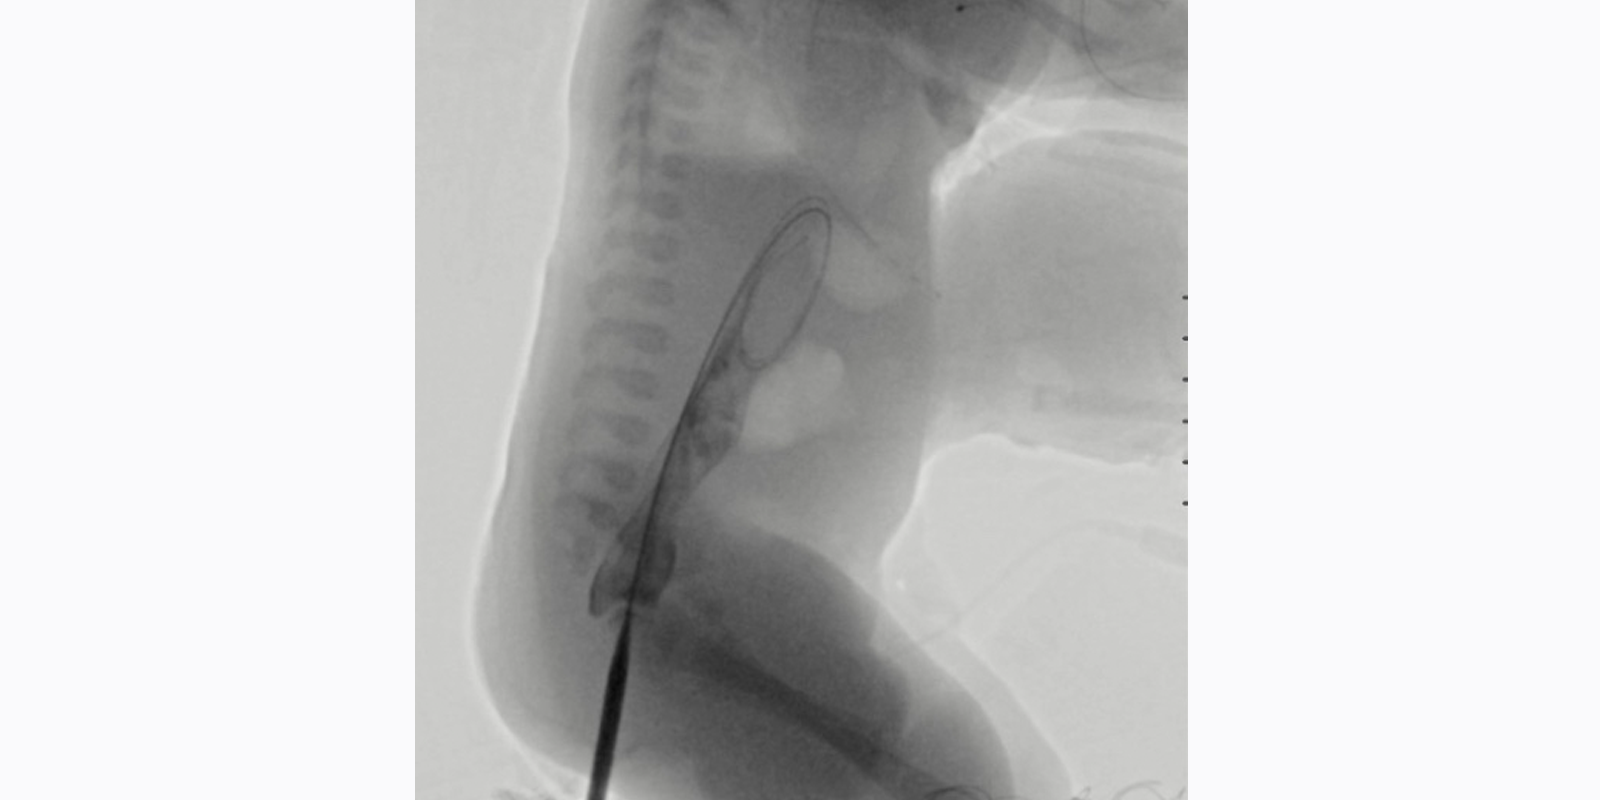

Over a period of six weeks, the team progressively dilated the neo-anorectal tract under fluoroscopic guidance. “It was a nice combination of skill sets and we had regular conversations about when to safely upsize the tract and how to manage it exactly,” Dr. Bertino says. “So it was a good long-term collaboration.”

Seldinger technique allowed for serial dilation of the neo-anorectal tract under fluoroscopic guidance. Source: NYU Langone Health.

Inserting a stiff wire through the neo-anorectal tract allowed for serial dilation of the tract under fluoroscopic guidance. Source: NYU Langone Health.